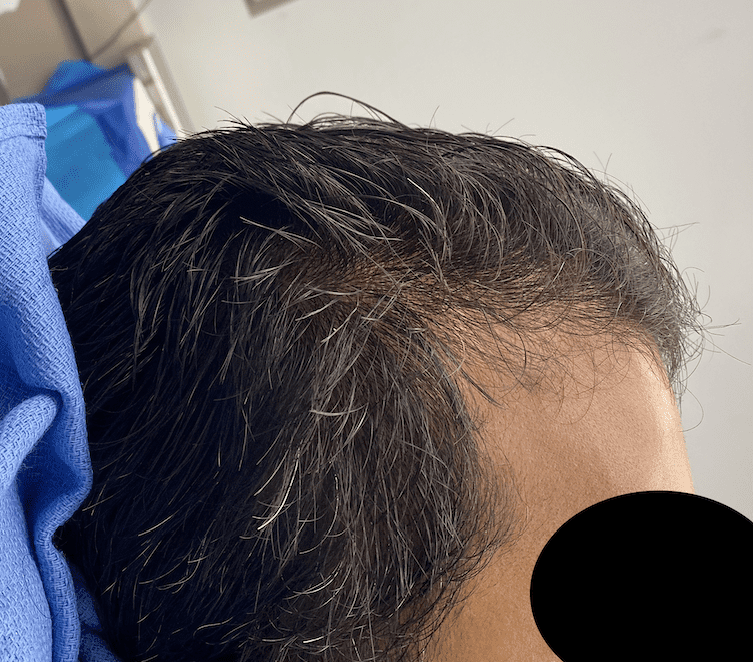

Desire for taller and rounder head shape.

Two stage custom skull implant augmentation technique.

Desire for taller and rounder head shape.

Two stage custom skull implant augmentation technique.